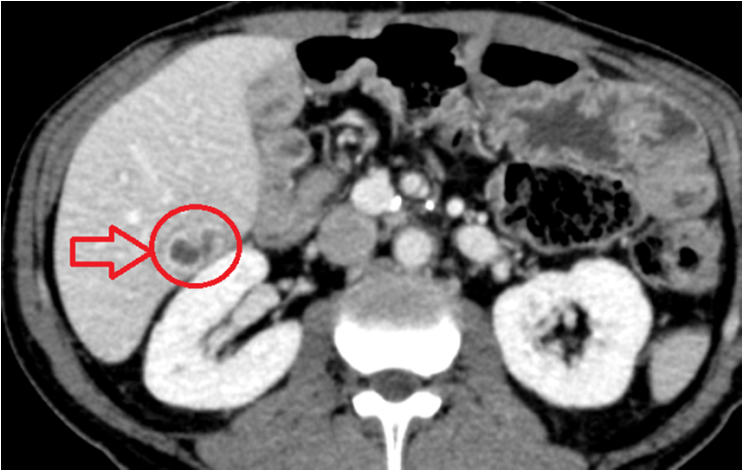

2. 간염 & 간농양 &간암

피로감, 미열, 우상복부의 뻐근한 불편감, 그리고 황달이 특징입니다. 간농양은 고열과 심한 통증이 동반되고 응급 처치가 필요한 경우도 있습니다.